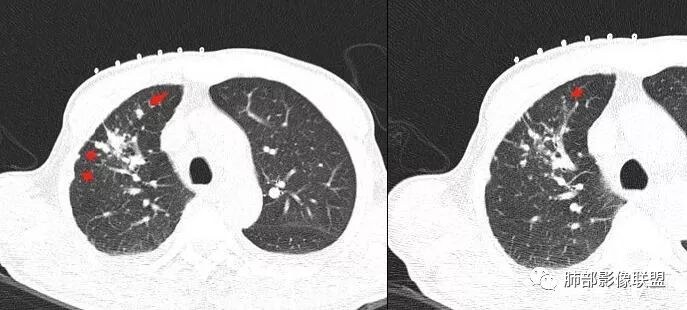

深分叶、边缘膨隆、胸膜凹陷征及附近多发结节,胸膜不干净,纵隔多发淋巴结

甄德强:附近结节是不是卫星病灶南边:不一定是卫星灶三个石头:是不是只有结核才能说卫星灶吧甄德强:局部确实有膨隆南边:

但是呢,我觉得这个病灶,它确实有一些恶性的特点,边缘膨隆,深分叶,有深短毛刺。

感觉胸膜上有很多结节,层面不够,还有一点胸水。

南边:纵隔淋巴结有融合的迹象,边界不清,右侧内乳动脉增粗了很多;怀疑纵隔淋巴结用血很大。有结核的话并不代表不能得癌肿;一般情况下结核附近的病灶呈条索树芽状;综上所述恶性不能完全排除。

2.右肺上叶斑片影、结节影、硬树丫,密度均匀未见钙化或液化。近胸壁处见分叶结节影及棘状突起,胸膜牵拉凹陷。

影像可以符合继发性肺结核或其他慢性炎症,或者说它们是存在的。

3.近胸壁处边缘分叶结节影,胸膜凹陷等使人怀疑基础疾病上出现新生物的可能性。

4.细看病灶有些散,有堆砌感。注意结核灶也常有胸膜牵拉。

增强扫描是应当的,对于区分结核灶拟或是肺腺癌有较大价值。病理检查还是必要的。

5.病理报告意犹未尽,引为憾事。这类肉芽肿炎更符合结核或非结核分枝杆菌感染。